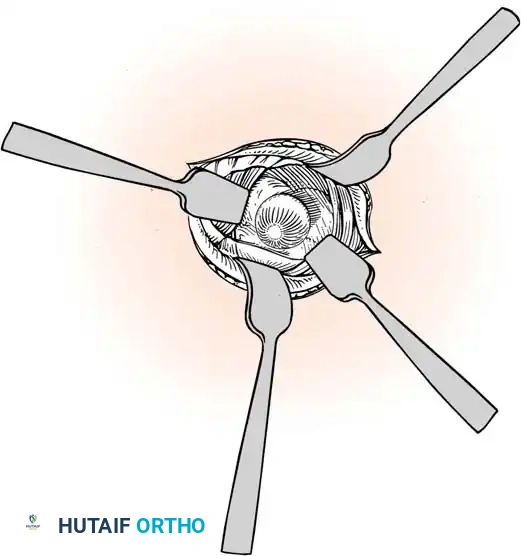

Careful separation of the ganglion from the surrounding extensor tendon sheaths.

- Stalk Excision: Using a combination of sharp and blunt dissection, mobilize the ganglion in its entirety. Trace the stalk down to its capsular origin at the dorsal scapholunate ligament. Excise the cyst along with a 1-cm margin of the dorsal capsule. Do not excise the substance of the scapholunate interosseous ligament itself, as this will cause carpal instability.

Excision of the ganglion stalk along with a generous margin of the dorsal joint capsule.